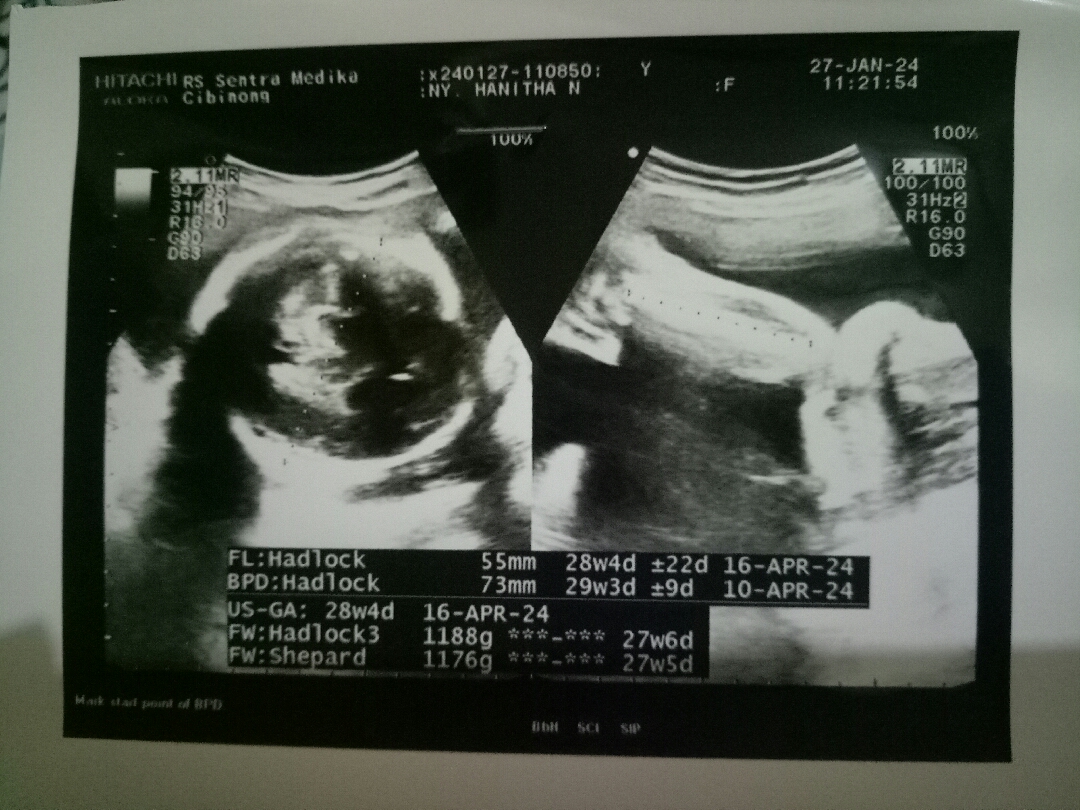

Usg bulan lalu

Aku pas usg 6 bulan ga keliatan krn ketutupan ari2. Pas 7 bulan usg, malemnya papa si dd elus2 perut minta tolong kasih liat mukanya ya de, mau liat mama papanya. Eh alhamdulillah dikasih liat dia lg garuk2 pipi jelas bgt🤭 Pulangnya baru makan eskrim, kebalik sih harusnya makan eskrim dulu, tp kayanya si dd nurut sama papanya😂